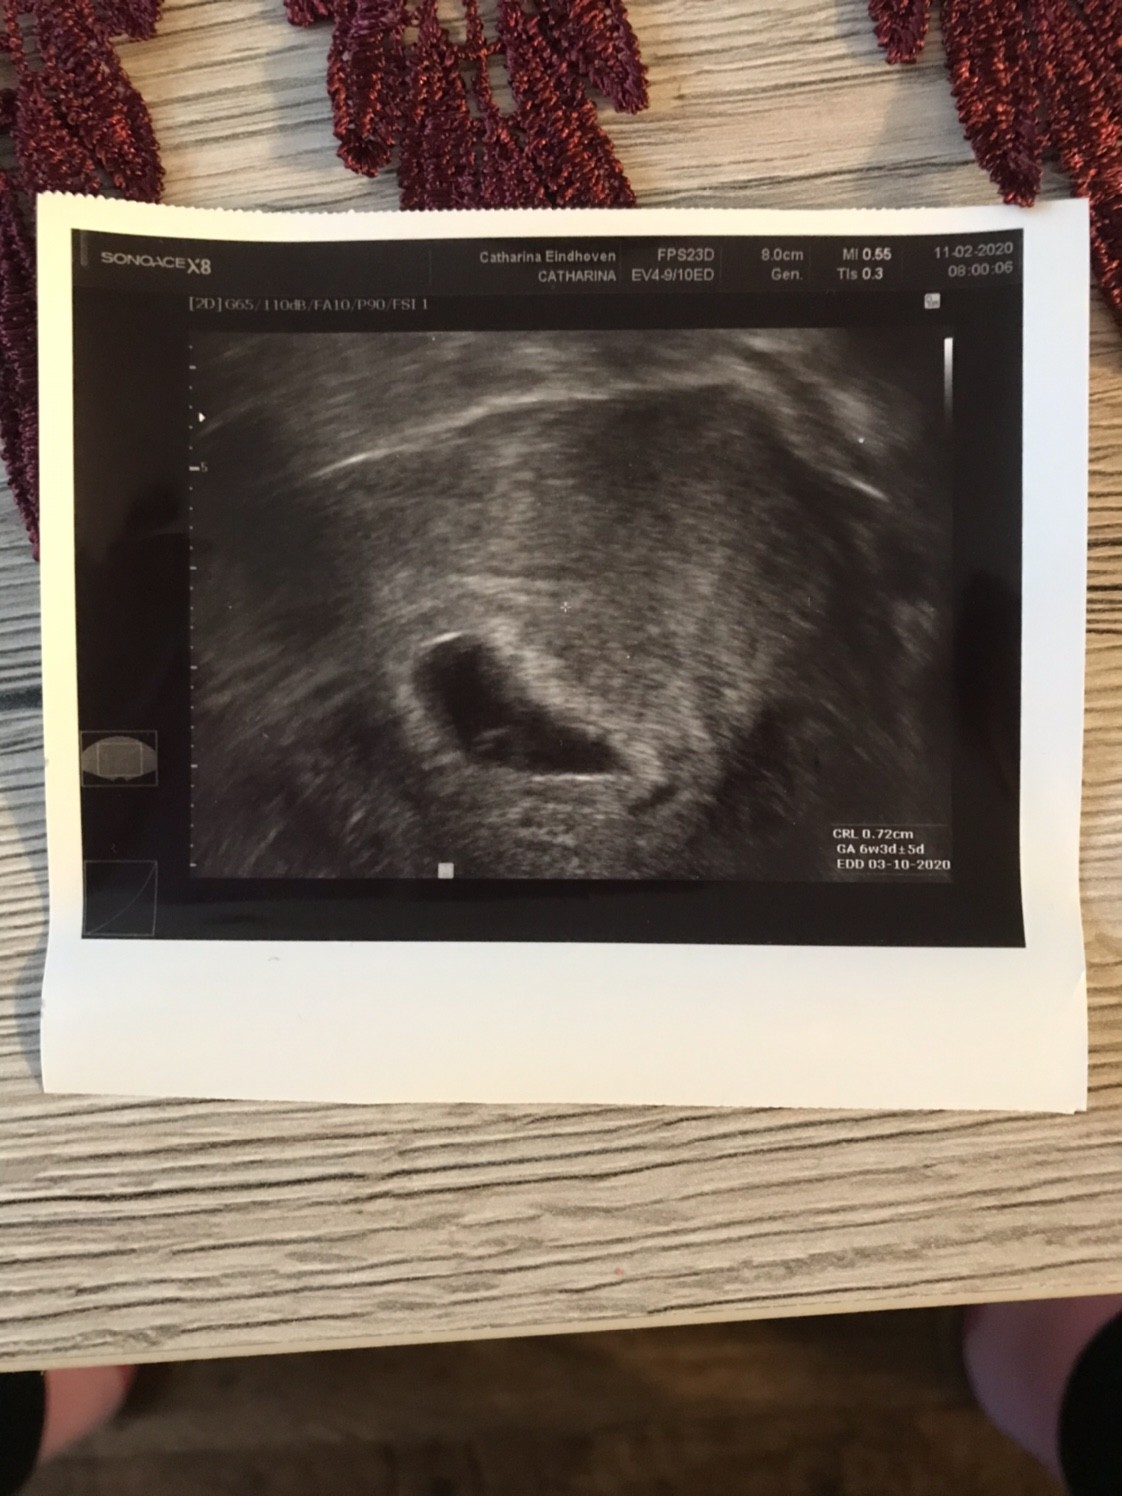

Jej!!! Piekny!!!!! Cudownie [emoji7][emoji7][emoji7]Dziewczynki chciałabym Wam przedstawić mój zarodeczek, na razie nie ma serduszka - albo go nie widać, za tydzień (18.02) usg serduszkowe. Wg usg 6t3d czyli pokrywa się z wyliczeniami. Jestem szczęśliwa i spokojna.

Zobacz załącznik 1078804